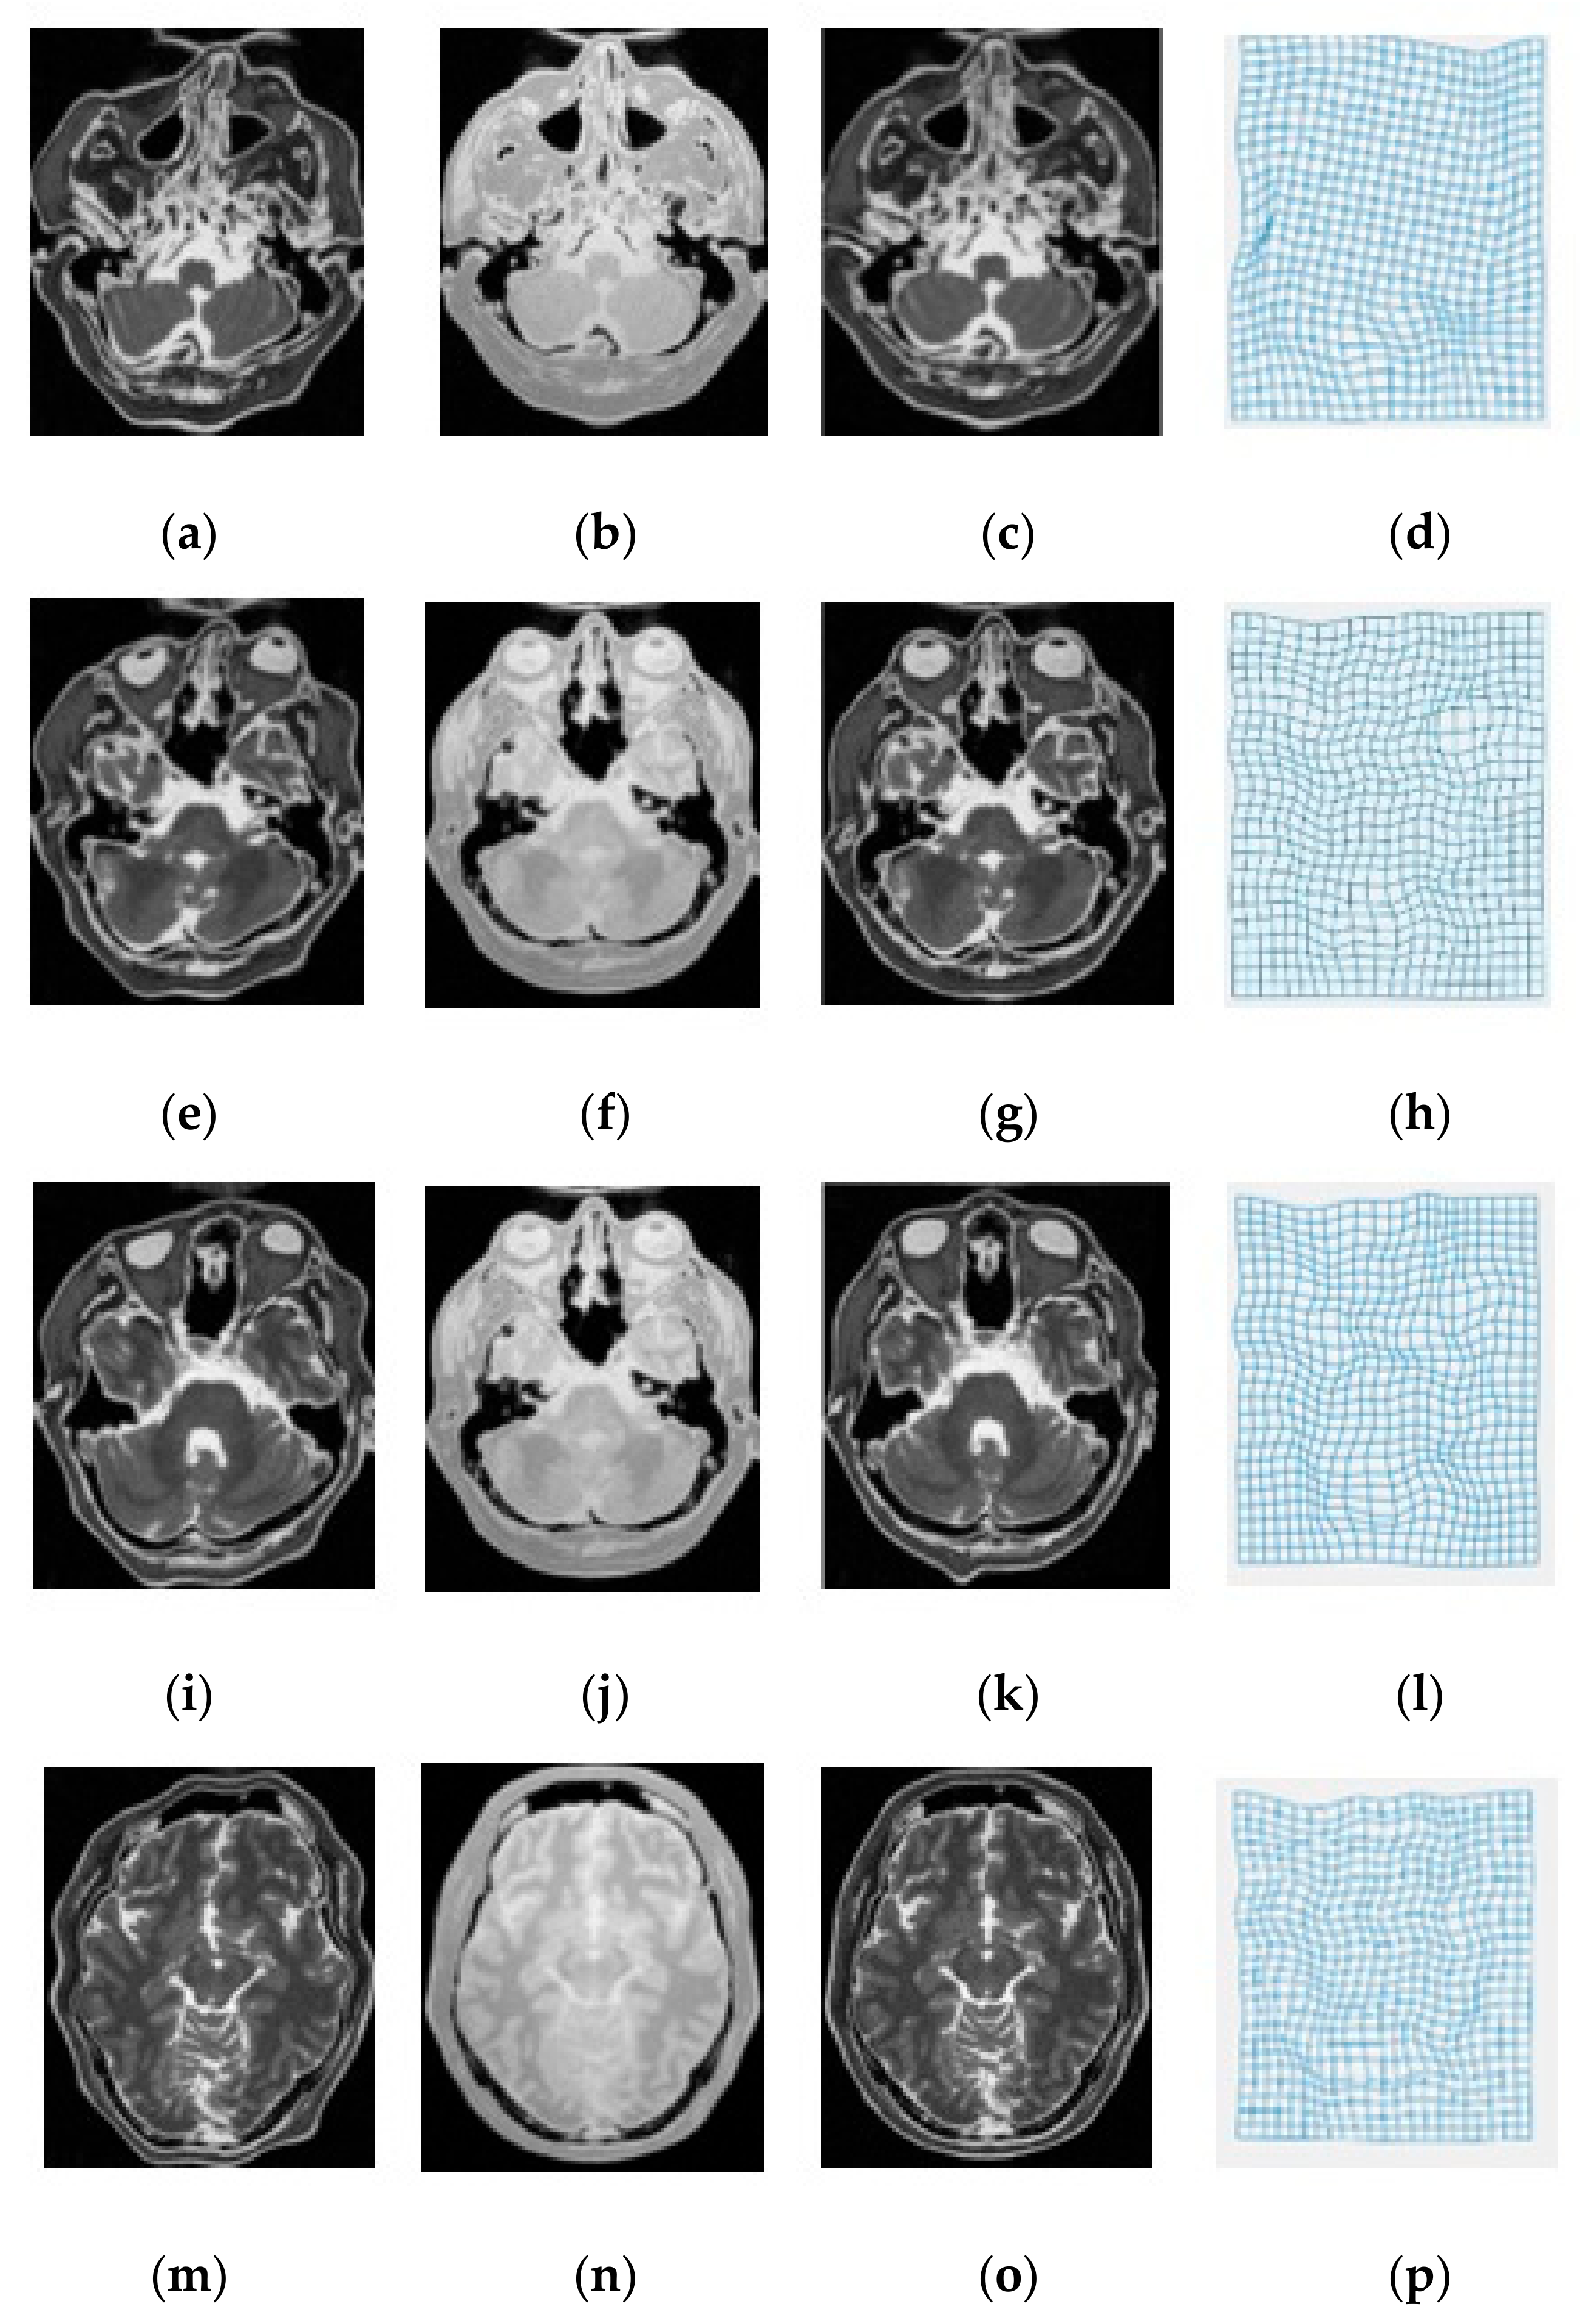

3. Experimental Results and Discussion

| Modality | MI [6] | SSC [21] | miLBP [25] | Ssesi [23] | miRID |

|---|---|---|---|---|---|

| T1-T2 | 2.63 | 2.35 | 2.42 | 2.45 | 2.04 |

| T1-PD | 2.88 | 2.16 | 2.26 | 2.42 | 2.13 |

| T2-PD | 3.01 | 2.47 | 2.36 | 2.47 | 2.01 |

| Average TRE | 2.84 | 2.33 | 2.35 | 2.45 | 2.03 |

| Average Time | 42.8 s | 39.6 s | 26.2 s | 35.4 s | 27.4 s |